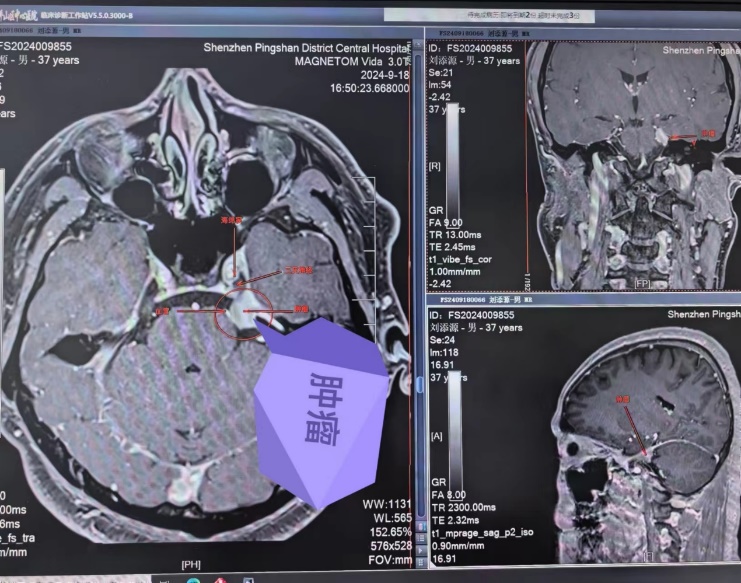

患者因出现左侧面部麻木症状已有一周时间,在外院检查后被确诊为颅内肿瘤。在焦虑和无助之际,患者慕名找到了深圳市坪山区中心医院神经外科陈建良教授。陈教授接诊后,迅速为患者进行了核磁共振增强等相关检查。结合患者的病史、临床症状以及影像学检查结果,确诊为左侧岩骨尖脑膜瘤,该肿瘤累及到三叉神经、海绵窦、岩静脉及脑干,需手术切除。

9月26日,由神经外科陈建良教授和李奇主任共同主刀,在麻醉科、手术室团队及相关科室的紧密配合和全程监测下,借助高倍手术显微镜的精准辅助,手术团队成功地暴露了手术区域,同时小心翼翼地保护了周围的血管、三叉神经及脑干等重要结构。经过4个小时的努力,最终成功完整地切除了肿瘤。